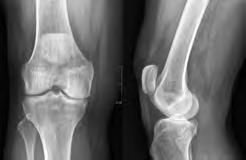

Total Knee Replacement

Total knee replacement is also called total knee arthroplasty. It is surgery that is done to remove and replace (or resurface) the worn parts of your knee joint. The knee is made up of the lower end of the thighbone (femur), the upper end of the shin bone (tibia), and the kneecap (patella), which slides in a groove on the end of the femur. Large ligaments attach to the femur and tibia to provide stability. The long thigh muscles give the knee strength. The joint surfaces where these three bones touch are covered with articular cartilage, which cushions the bones and enables them to move easily. A thin membrane releases a special fluid that lubricates the knee, reducing friction during movement. Normally, all of these components work in harmony. However, disease or injury can cause pain, muscle weakness, and reduced function. If you have these problems, you may need to have a total knee replacement.

During the total knee replacement, the damaged surfaces of your knee joint are removed and replaced with an implant. This implant may be made of metal and/or plastic. Total knee replacement surgery may decrease or take away your knee pain and make standing, sitting, and walking easier.

Normal knee joint